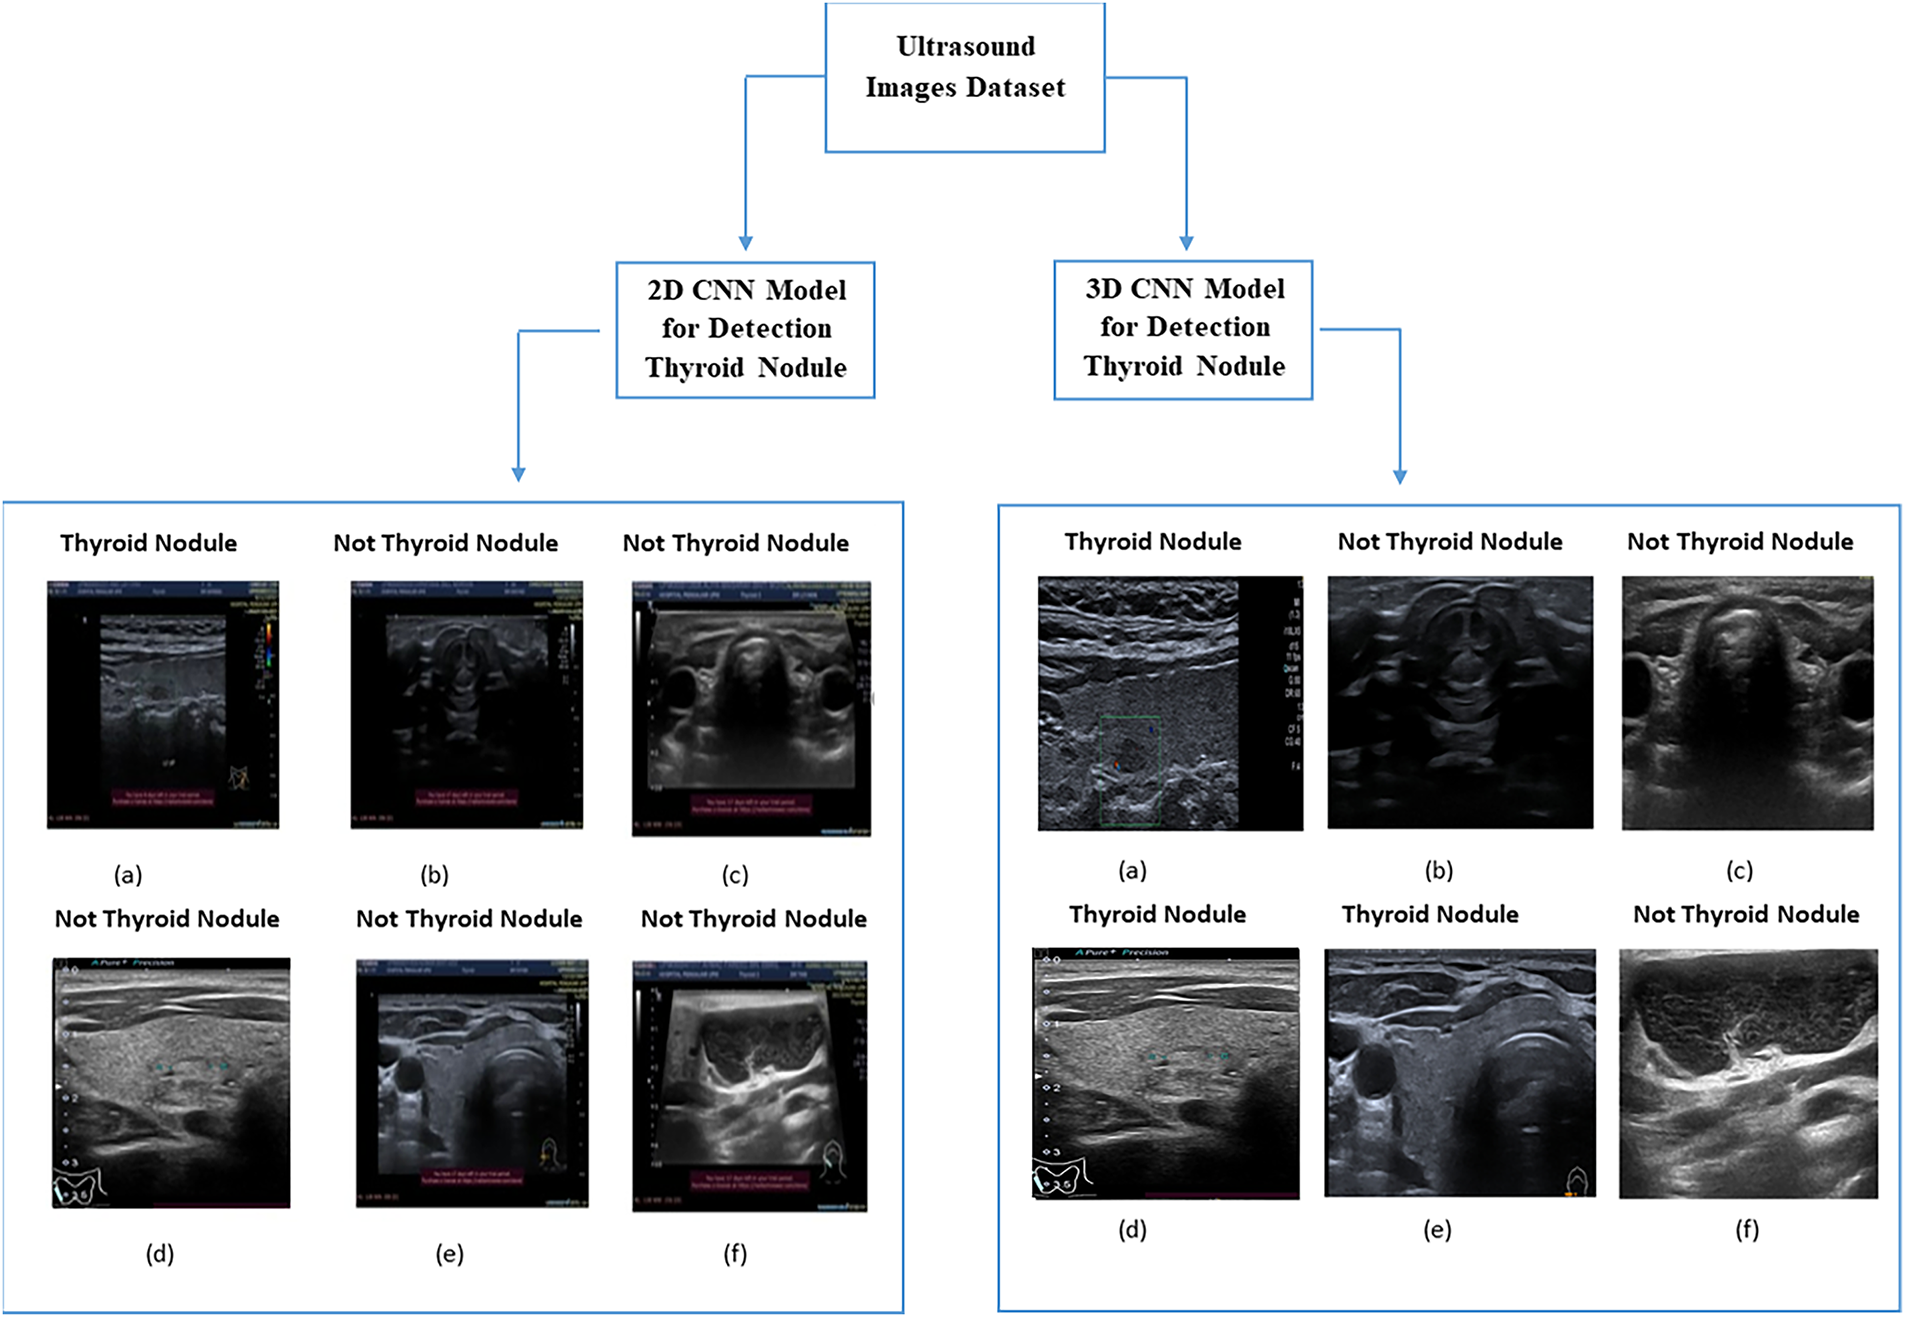

5 Comparison between 2D and 3D CNNs

Fig. 11 shows a comparison between the 2D and 3D CNNs used to detect thyroid nodules of different sizes (large and small). As shown in image (a), the 2D CNN model on side (A) detected thyroid nodules with a size of 4 mm from ultrasound images.

Figure 11: Comparison between 2D CNN and 3D CNN

In contrast, images (d) and (e) show that the 2D CNN model could not accurately detect thyroid nodules with sizes of 1 and 3 mm (images (d) and (e), respectively). However, the 2D CNN model correctly identified images not containing thyroid nodules, reaching an accuracy of 92%. In general, the images detected using the 2D CNN model contained large thyroid nodules. In contrast, the 3D CNN model detected all images containing various sizes of thyroid nodules because of its ability to extract volumetric features and representative features from ultrasound images. Therefore, the 3D CNN model can detect small nodules more accurately than the 2D CNN model. This is consistent with the medical imaging results and the detection accuracy of pathological tissues reported in [37].

Table 10 shows a comparison between the two models regarding their nodule detection performance. The metrics used in the comparison include precision, recall, F1 score and accuracy. The 2D CNN model achieved remarkable results, particularly in terms of accuracy, but could not detect small nodules [35]. The proposed 3D CNN model detected all nodule sizes because of its ability to extract high-level nodule features [26]. In the dataset used for comparing the two models, 36 images contained thyroid nodules with a size of ≤3 mm. The 2D CNN model successfully detected 20 of these images, where the nodule size was 3 mm; it could not detect nodules with a size of ≤2. In contrast, as shown in Table 10, the 3D CNN successfully detected 31 images containing small nodules, indicating its efficiency in extracting all features. Furthermore, the proposed 3D CNN model was tested using clinical ultrasound images obtained from SAASH in Malaysia by an experienced radiologist with more than 10 years of experience.